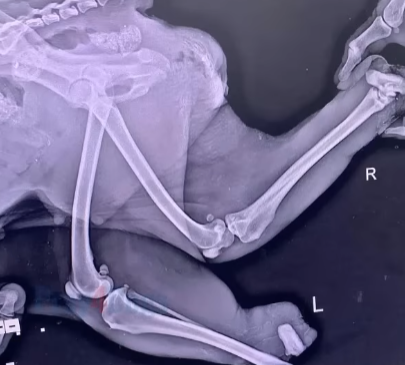

At the veterinary clinic, the truth came out slowly. Severe injuries. Infection. Dehydration. She had been suffering for days—maybe longer—surviving on nothing but rainwater and hope.

“She shouldn’t have made it,” the vet said quietly. “But she kept trying.”